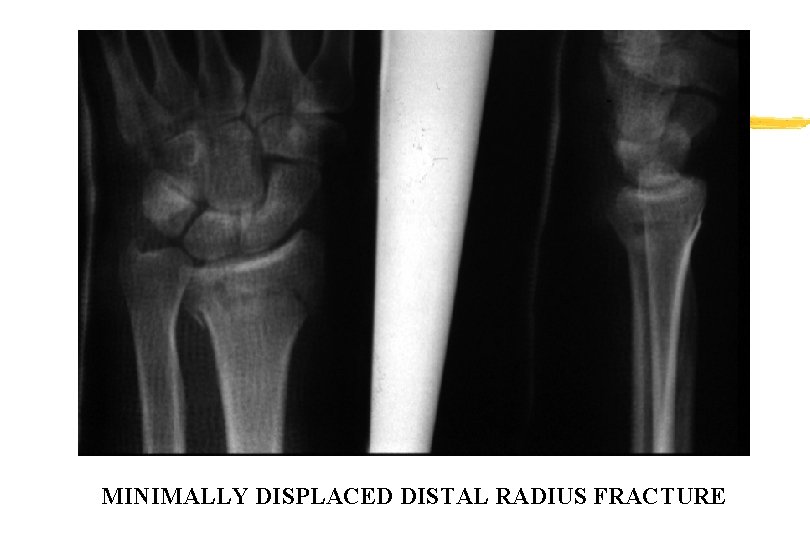

MINIMALLY DISPLACED DISTAL RADIUS FRACTURE